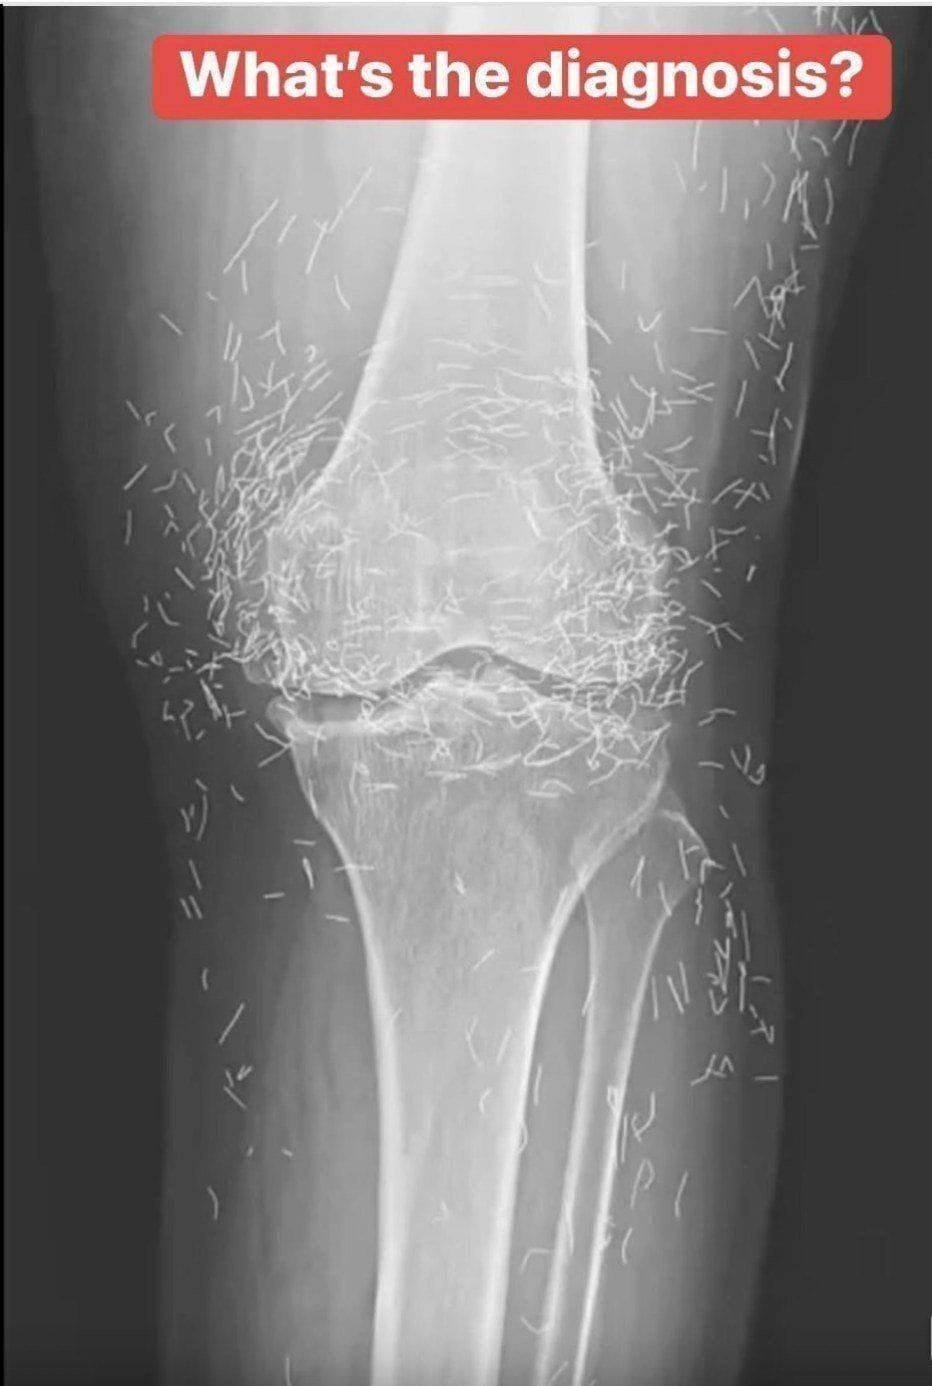

Years later, when doctors took X-rays to evaluate her knee condition, they weren’t prepared for what appeared on the images. Her knees were filled with dozens of bright, metallic flecks — tiny needles embedded deep within the joint area.

The findings were later documented in a case published by the New England Journal of Medicine.

Beyond inflammation, the needles created another problem: imaging complications. Metal objects can obscure parts of the anatomy on X-rays, making it harder for doctors to clearly assess joint damage or disease progression.

Even more concerning, the presence of metal inside the body can make certain scans dangerous. MRI machines rely on powerful magnetic fields, and embedded needles may shift during scanning, potentially damaging blood vessels or surrounding tissue. In short, future diagnostic options for this patient became limited.